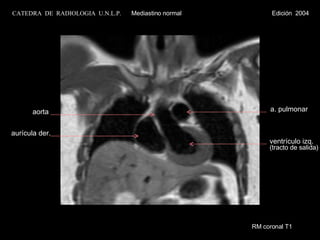

RM coronal T1 ventrículo izq. (tracto de salida) a. pulmonar aurícula der. aorta CATEDRA  DE  RADIOLOGIA  U.N.L.P.   Mediastino normal  Edición  2004

RM coronal T1 aurícula der. a. pulmonar ventrículo izq. (tracto de salida) v. braquiocef. derecha v. braquiocef. izquierda tráquea CATEDRA  DE  RADIOLOGIA  U.N.L.P.   Mediastino normal  Edición  2004

RM coronal T1ventrículo izq. (tracto de salida) a. pulmonar aurícula der. aorta CATEDRA DE RADIOLOGIA U.N.L.P. Mediastino normal Edición 2004

RM coronal T1aurícula der. a. pulmonar ventrículo izq. (tracto de salida) v. braquiocef. derecha v. braquiocef. izquierda tráquea CATEDRA DE RADIOLOGIA U.N.L.P. Mediastino normal Edición 2004